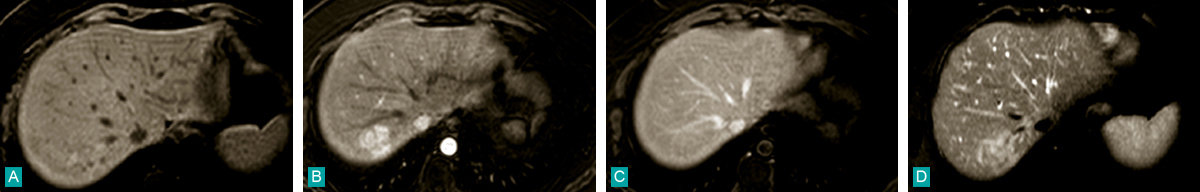

A. T1 sans iv. ; B. T1 art. ; C. T1 portal. ; D. T2 spir.